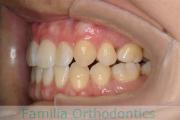

No.23V-061

- 主な症状:

- 叢生

- その他の症状:

- 上下顎前突

- 年齢:

- 23歳

- 性別:

- 女性

- 抜歯部位

- 上:

- 44

- 下:

- 主な使用装置:

- FEA 022

- 治療にかかった費用:

- 88万円

でこぼこを綺麗に並べたいということで来院されました。上下左右から小臼歯を抜歯して、マルチブラケット法を2年半、30回程度通院していただいて行いました。

かなり強い叢生(でこぼこ、凹凸、ガタガタ)のため、保定をしっかりしないと後戻りのリスクが高いケースといえます。